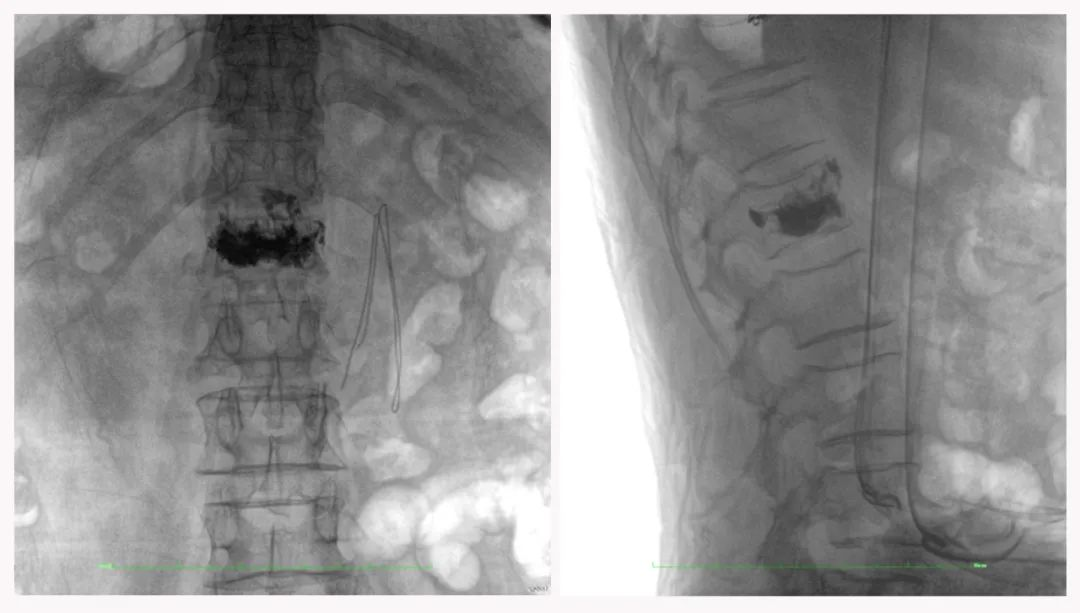

病例3:超聲支氣管鏡下肺活檢(80歲)

三維C形臂還可以創(chuàng)新性地應(yīng)用在呼吸介入領(lǐng)域。例如,在經(jīng)皮穿刺或經(jīng)支氣管鏡肺結(jié)節(jié)活檢、定位、消融等場(chǎng)景中,用于確認(rèn)工具是否到達(dá)病灶、消融范圍是否完全覆蓋病灶等。

二維影像無法準(zhǔn)確判斷工具是否到達(dá)病灶

三維各切面影像都顯示工具達(dá)到病灶內(nèi)